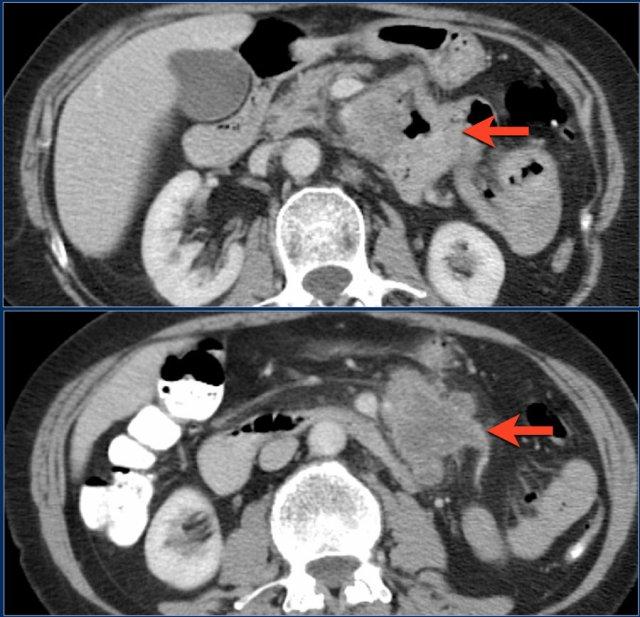

Đây là một trường hợp ung thư biểu mô tuyến khác ở hỗng tràng.

Có nhiều hạch bạch huyết (mũi tên đỏ) và thâm nhiễm mỡ (mũi tên vàng).

Không nên nhầm lẫn với viêm mỡ mạc treo vì các hạch bạch huyết hoại tử lớn này là bệnh lý.